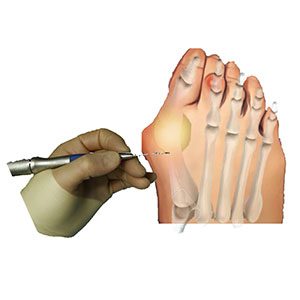

Cirugía percutánea

En la mayoría de las patologías del antepié (hallux valgus, rigidus, metatarsalgias, deformidad de los dedos) realizamos cirugía percutánea conocida popularmente como “láser”. Esto nos permite corregir las deformidades con un mínimo daño a las partes blandas y sin apenas cicatriz lo que traduce menos dolor y una recuperación más rápida.

En el hallux valgus y en las fases incipientes del hallux rigidus fijamos la corrección deseada con tornillos (cirugía percutánea de 3ª generación) lo que confiere más estabilidad y por tanto nos permite conseguir unas mayores correcciones de la deformidad sin apenas dolor respecto a otras técnicas percutáneas.